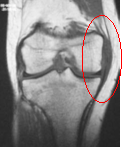

Collateral ligaments

n MCL tear

T2 sag

Edema at

site of torn

ligament